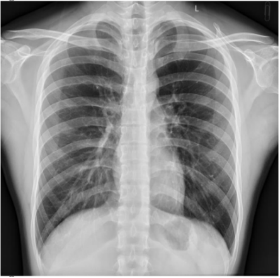

车载数字化X射线成像系统配置及参数:

DXR-560系列车载式数字化X射线摄影系统是七喜医疗专为移动体检车设计的一款高品质产品。伸筒式设计,一体成型机架,在保证高机械强度的同时大幅降低整体重量,更适合安装在体检车内;高速、大容量的工作站存储空间可存储20000幅图像;**与图像处理软件合二为一,在检查的同时可便捷打印报告;符合DICOM标准的通讯协议和多种硬件接口配置方便与**HIS、RIS、PACS等系统互通互联。

High Quality Image **的图像质量

**的影像链,图像**

超高分辨率平板探测器

平板探测器是高品质图像的保证,采用目前业内**为**的1100万级像素静态非晶硅平板探测器;以较低的射线剂量展现更多图像细节的同时将噪声降****;从根本上保证了图像质量。

业内超高的总像素值,超高的空间分辨率,以及密度分辨率保证了平板探测器在低剂量的条件下亦能为您提供更多的图像细节。

43cm×43cm的平板探测器,使您在检查任何部位时均无后顾之忧。大尺寸平板,有效解决体型人群胸片等大体位的投照摆位问题。减少检查中烦琐的摆位,使诊断更为轻松便捷。